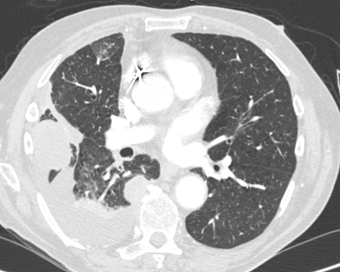

The second mass was noted adjacent to the right side

aspect of T8 and T9 vertebral bodies and measured 2.0 x 2.6cm (figure 3).

There was also associated pleural

thickening in the right costophrenic angle with an associated pleural based

lesion measuring 2.0 x1.9cm as well as a right hilar node which was 1.4cm (figure 4).

Figure 3. The second mass was noted adjacent to the

right side aspect of T8 and T9 vertebral bodies.

Figure 4. Associated pleural thickening in the right

costo-phrenic angle with an associated pleural-based

lesion measuring 2.0 x 1.9 cm as well as

a right hilar node which was 1.4cm.